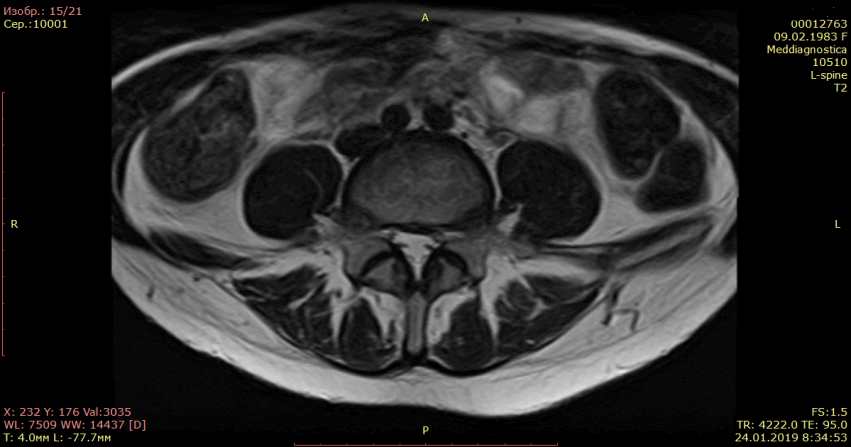

Осмотрели Ирину неврологически и ортопедически, исследовали позвоночник на МРТ и рентгене. Оказалось, что у нее очень большая левосторонняя грыжа размером 12 мм.

На МРТ показано излечение грыжи диска (до- и после лечения).

После первого же приема удалось выраженно уменьшить боль. Ночь Ирина уже спала. Дневные боли у значительно уменьшились уже через несколько дней. Возможность спать без боли – это тоже не мало.

Прошло 2 недели. Ирину практически ничего не беспокоило. Но, ногу поднять в полном объеме она еще не могла. Сохранялся т.н. симптом Ласега (боль в спине и ноге, когда пациент лежит на спине, а врач поднимает ногу). Это говорило о том, что грыжа еще сдавливает корешок.